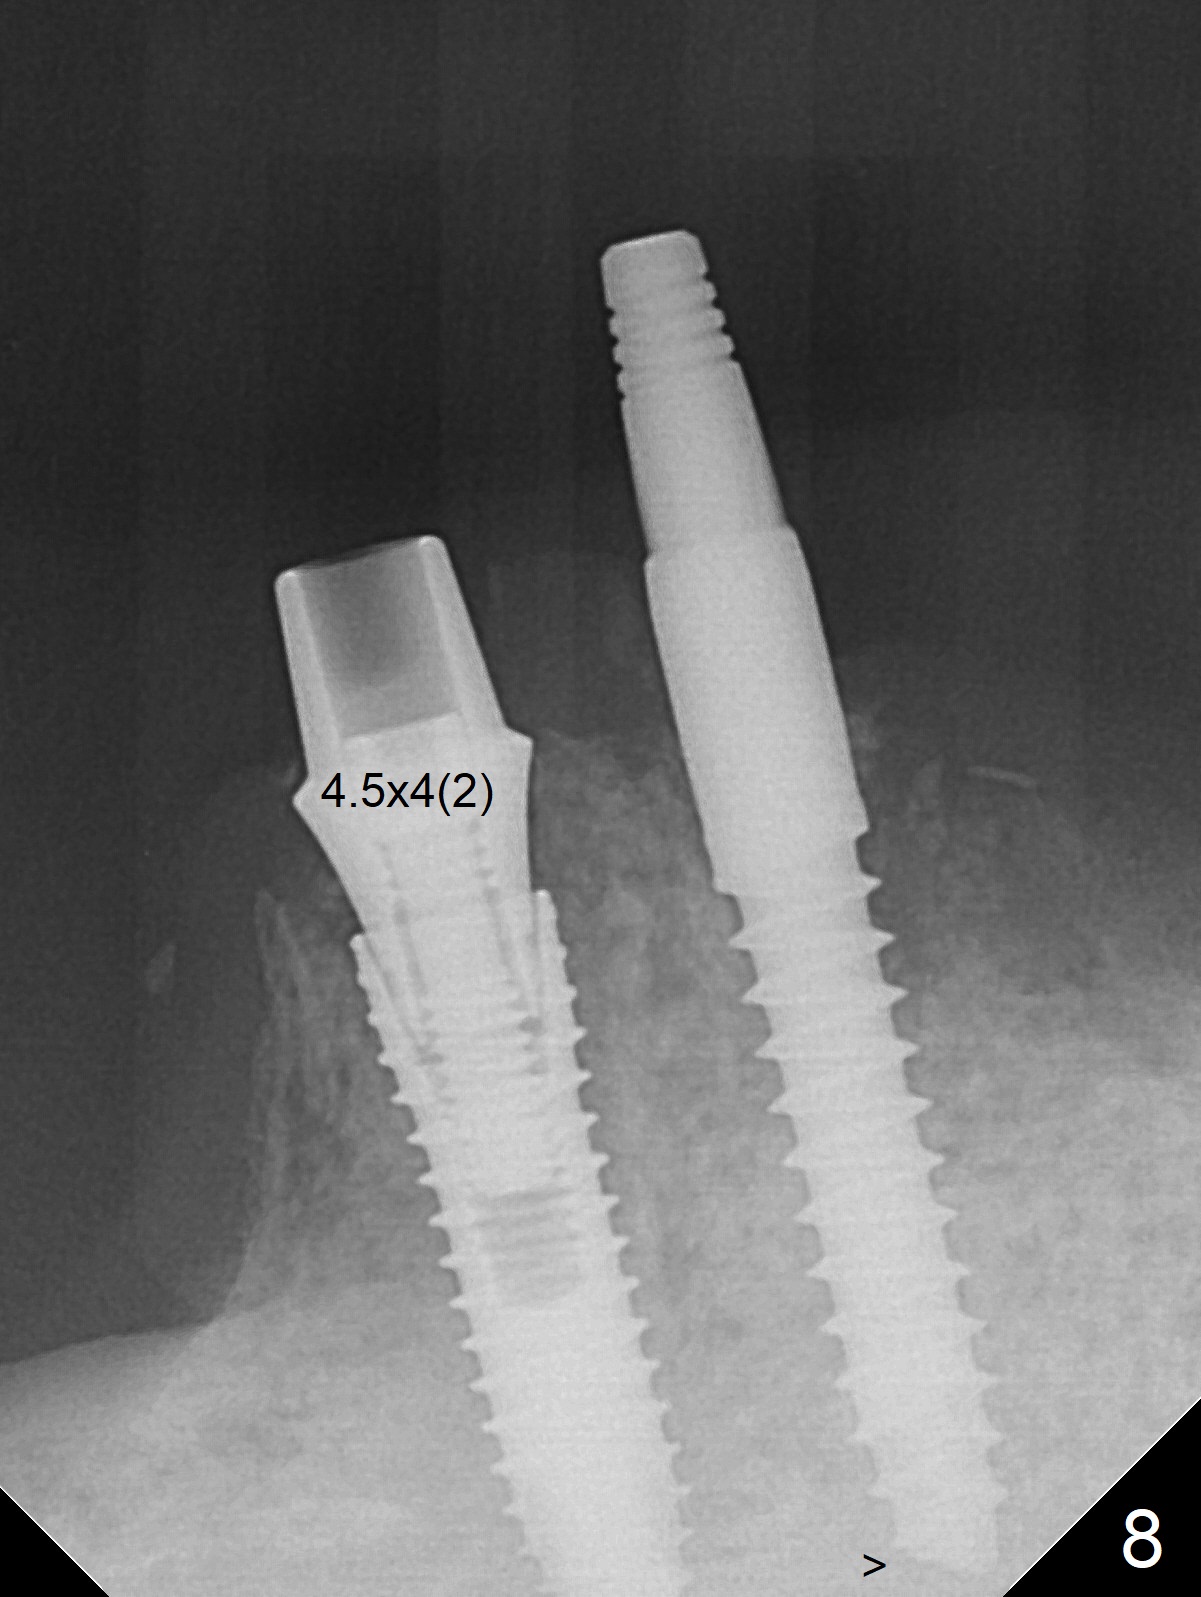

When the patient returns for #26 extraction and immediate implant and #27 RCT, it appears that the tooth #27 with subgingival margin distolingually is non-salvageable (Fig.1). She has dry mouth. Osteotomy is initiated in the lingual slope (Fig.4 red dashed line) of each socket with 1.2 and 2 mm drills for 16 and 19 mm at #26 and 27, respectively (Fig.2,3). The depth at #27 is subsequently reduced, while a 3x14(2) mm dummy implant is placed at #26 (Fig.5,6). A 3.8x13 mm implant is placed at #27 smoothly, while insertion of a 3x16(4) mm definitive implant (by mistake) has resistance (Fig.7). When the depth at #26 increases, there is feeling of perforation. The apex of the implant is truncated prior to reinsertion (Fig.8 >).